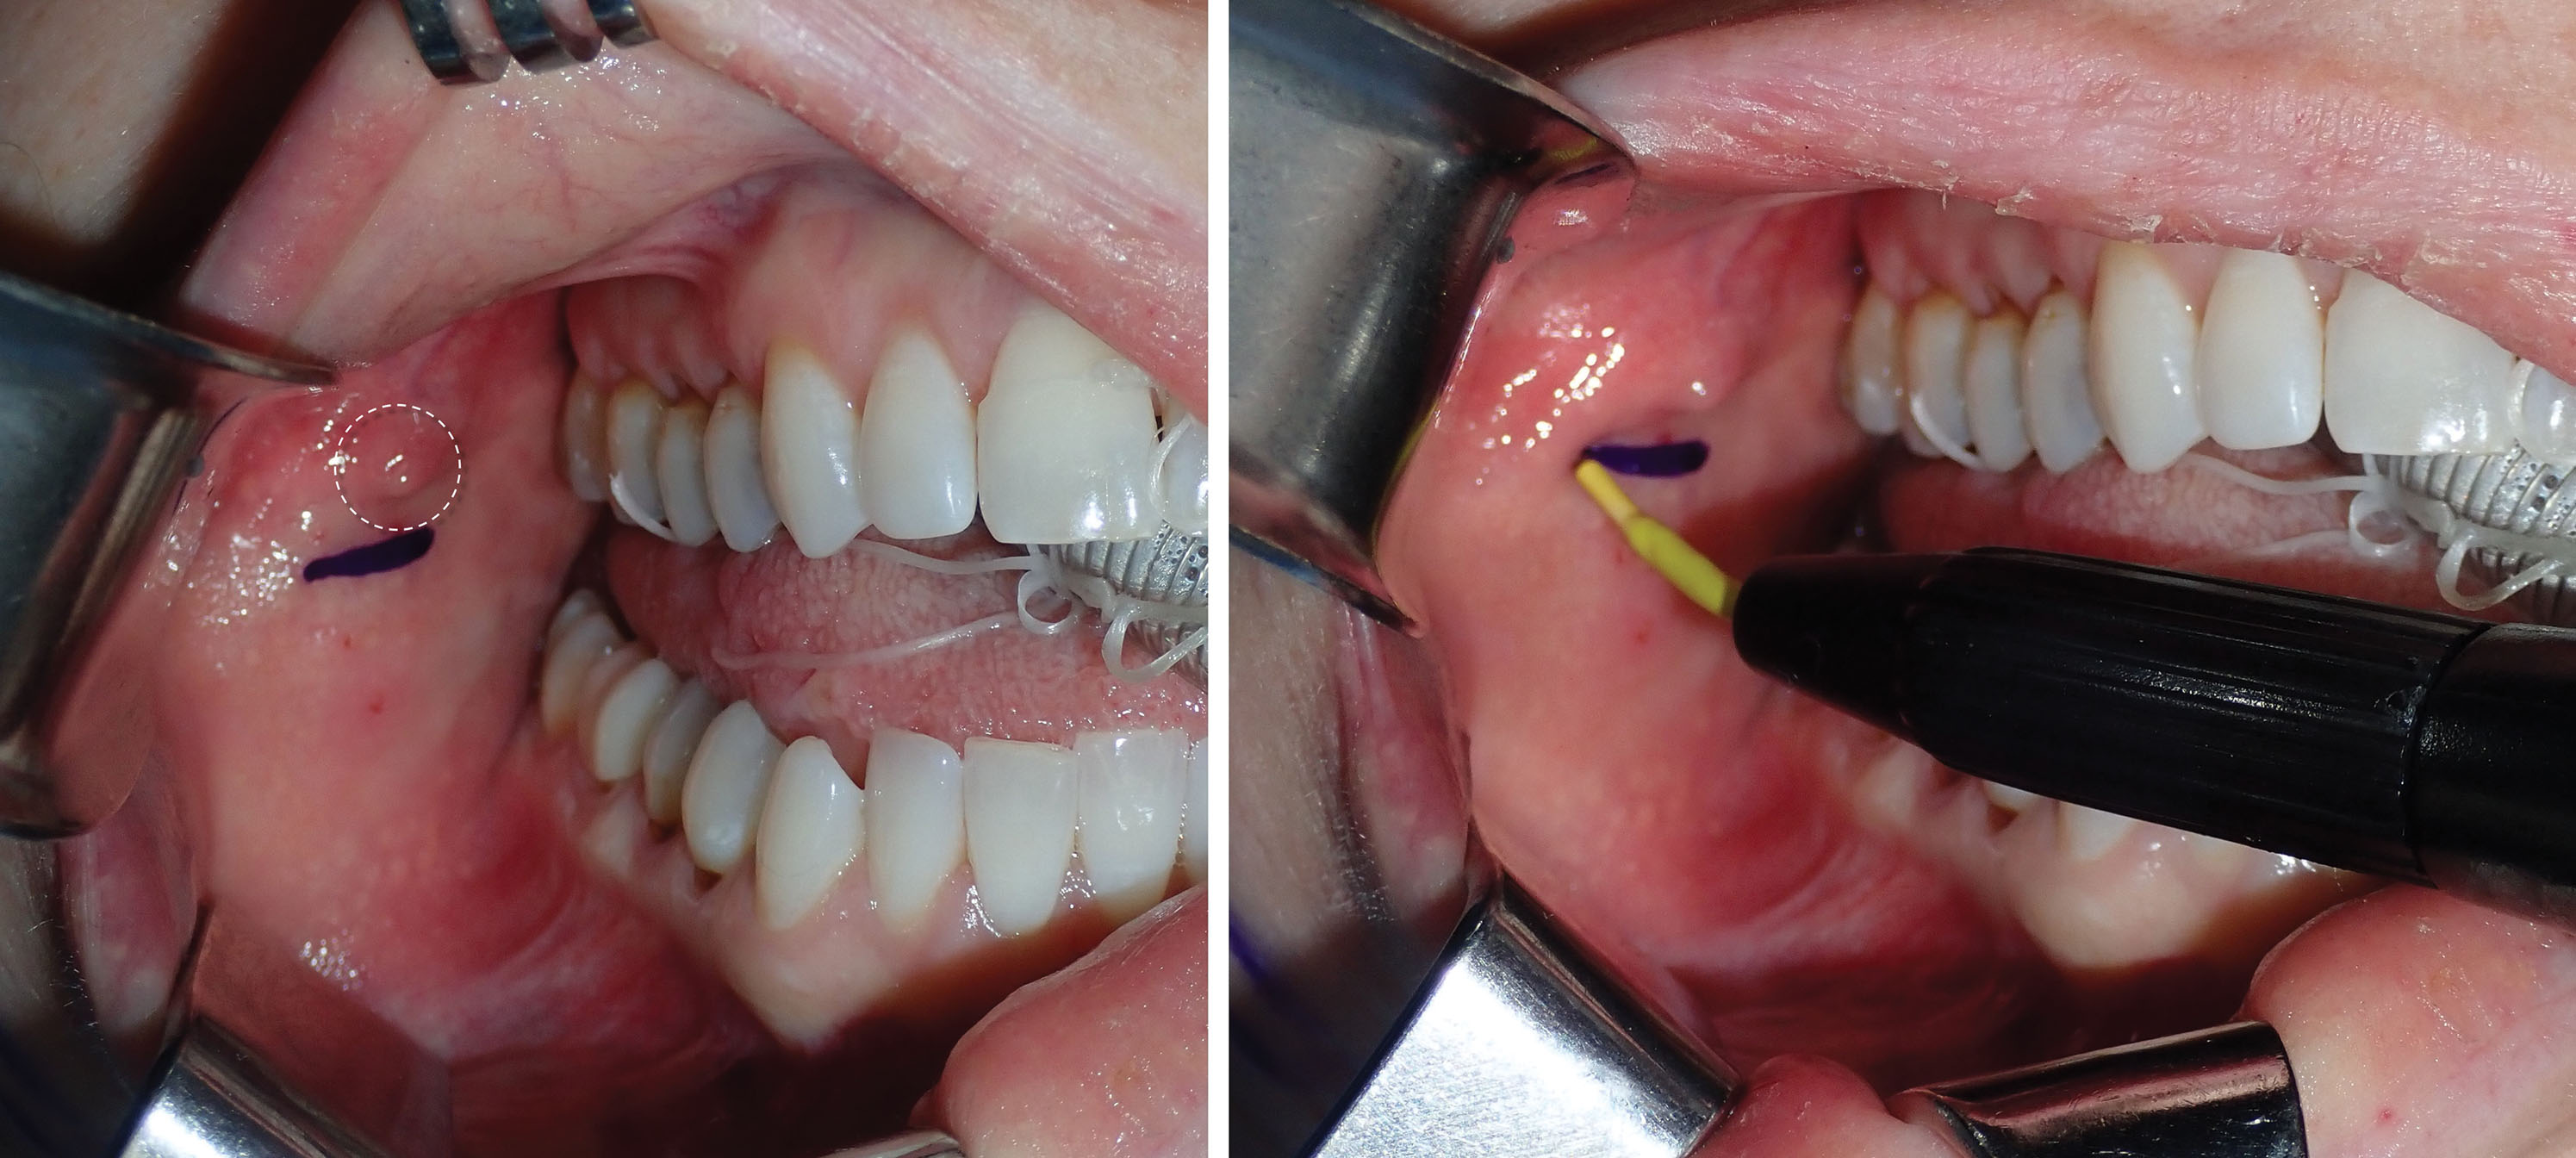

BFR can be easily performed with local anesthesia or intravenous sedation. The first step is to infiltrate the proposed incision site with local anesthesia. Approximately 2 mL of 2% lidocaine with 1:100,000 epinephrine is infiltrated just under the parotid duct (Stenson’s duct) into the mucosa. The duct is located opposite the first molar region on the cheek mucosa. On some patients it is very easy to see, and on others the orifice is more hidden. Several more milliliters of local anesthetic are infiltrated into the buccinator muscle (which is just submucosal) and into the generalized region to be reduced. I prefer to make the incision several millimeters below the parotid duct. In general, the BFP is easily located and reduced, but location can be challenging in some patients,. My first approach is always through the infraductal incision. If the fat cannot be located through this incision, my secondary mucosal approach (pterygoid approach) is more superior and lateral to the second and third molars in the maxillary sulcus.

As stated, a 4- to 5-mm-wide incision is made with a radiofrequency microneedle just through the mucosa several millimeters under the parotid duct ( Fig. 15.11 ). This area is very vascular, and a coagulative incision modality is preferred. The actual incision is made only through the mucosa as the vascular buccinator muscle can bleed significantly, and this is sometimes difficult to coagulate. The parotid and buccal branches of the facial nerve traverse the BFP, so blind coagulation is not desirable.